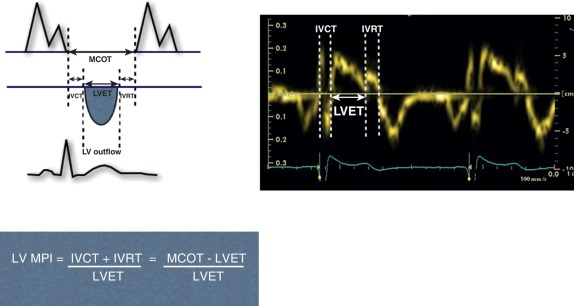

III. IVRT의 심장 초음파 측정: 기법 및 프로토콜

가장 일반적인 방법은 일반적으로 심첨 4 또는 5 방면도(apical 4 or 5-chamber view)에서 좌심실 유입/유출로 영역에 PW 도플러 샘플 용적(sample volume)을 위치시키는 것이다.3 목표는 대동맥 유출의 중단(수축기 박출 종료, 종종 대동맥 판막 폐쇄 클릭 인공물로 표시됨)과 승모판 유입의 시작(E파 시작)을 동시에 기록하는 것이다.3 기저선(baseline)은 종종 변환기 쪽으로 향하거나 멀어지는 혈류를 모두 표시하기 위해 중앙에 위치시킨다.10 샘플 용적은 승모판 유입과 대동맥 유출 경로 사이에 전략적으로 위치시킨다.10

IVRT는 대동맥 판막 폐쇄 인공물부터 승모판 E파 시작까지의 시간 간격으로 측정된다.1 샘플 용적 위치 및 동일 심박 또는 필요한 경우 연속적인 심박에서 두 판막 이벤트의 명확한 경계 표시에 주의해야 한다. 폐쇄 "클릭" 인공물을 사용하는 것이 일반적이다.10